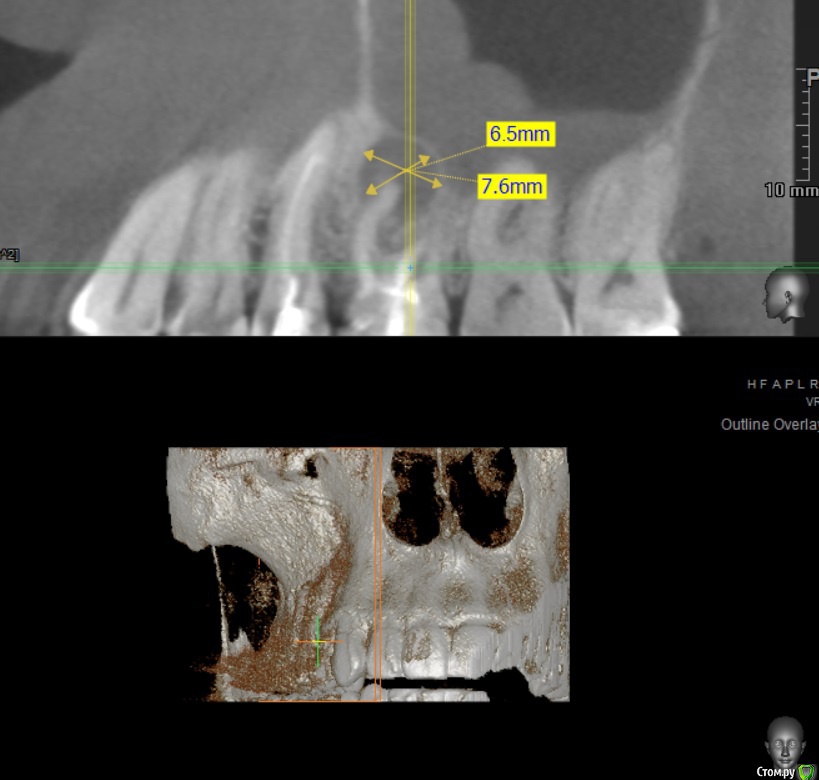

twodudu Опубликовано 12 декабря, 2019 Поделиться Опубликовано 12 декабря, 2019 (изменено) стоит проблема- удалить, чтобы не беспокоил .Или же лечить. Что скажите? зуб номер 6, находится вверху справа. На корне киста Изменено 12 декабря, 2019 пользователем twodudu Ссылка на комментарий

twodudu Опубликовано 18 декабря, 2019 Автор Поделиться Опубликовано 18 декабря, 2019 (изменено) подскажите еще, вопрос по гайморовой пазухе. Как она далеко, не прошло ли в нее воспаление? Сегодня был на приеме говорят, что вроде как очень близко Изменено 18 декабря, 2019 пользователем twodudu Ссылка на комментарий

red_butler Опубликовано 18 декабря, 2019 Поделиться Опубликовано 18 декабря, 2019 подскажите еще, вопрос по гайморовой пазухе. Как на далеко, не прошло ли в нее воспаление? Сегодня был на приеме говорят, что вроде как очень близкоБлизко, но это не страшно Ссылка на комментарий